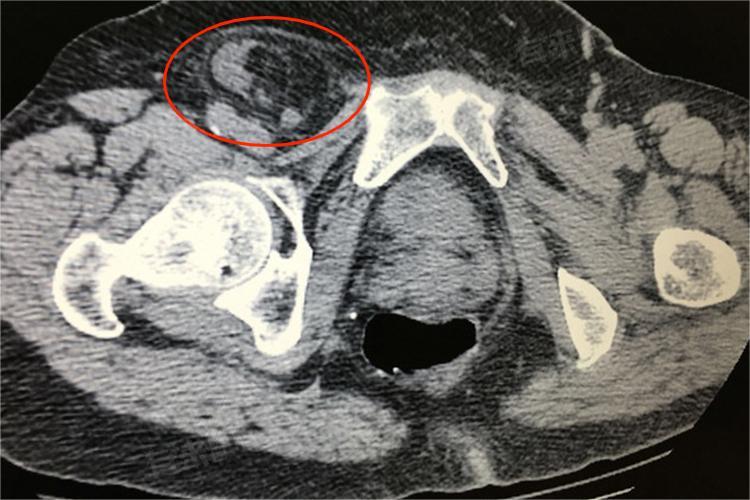

5、嵌顿疝的风险:疝气长时间未得到治疗,疝内容物容易发生嵌顿,即突出的组织无法回纳,导致血液循环障碍。这可能会引起疝内容物的缺血、坏死,引发严重的感染和腹膜炎,甚至可能危及生命。